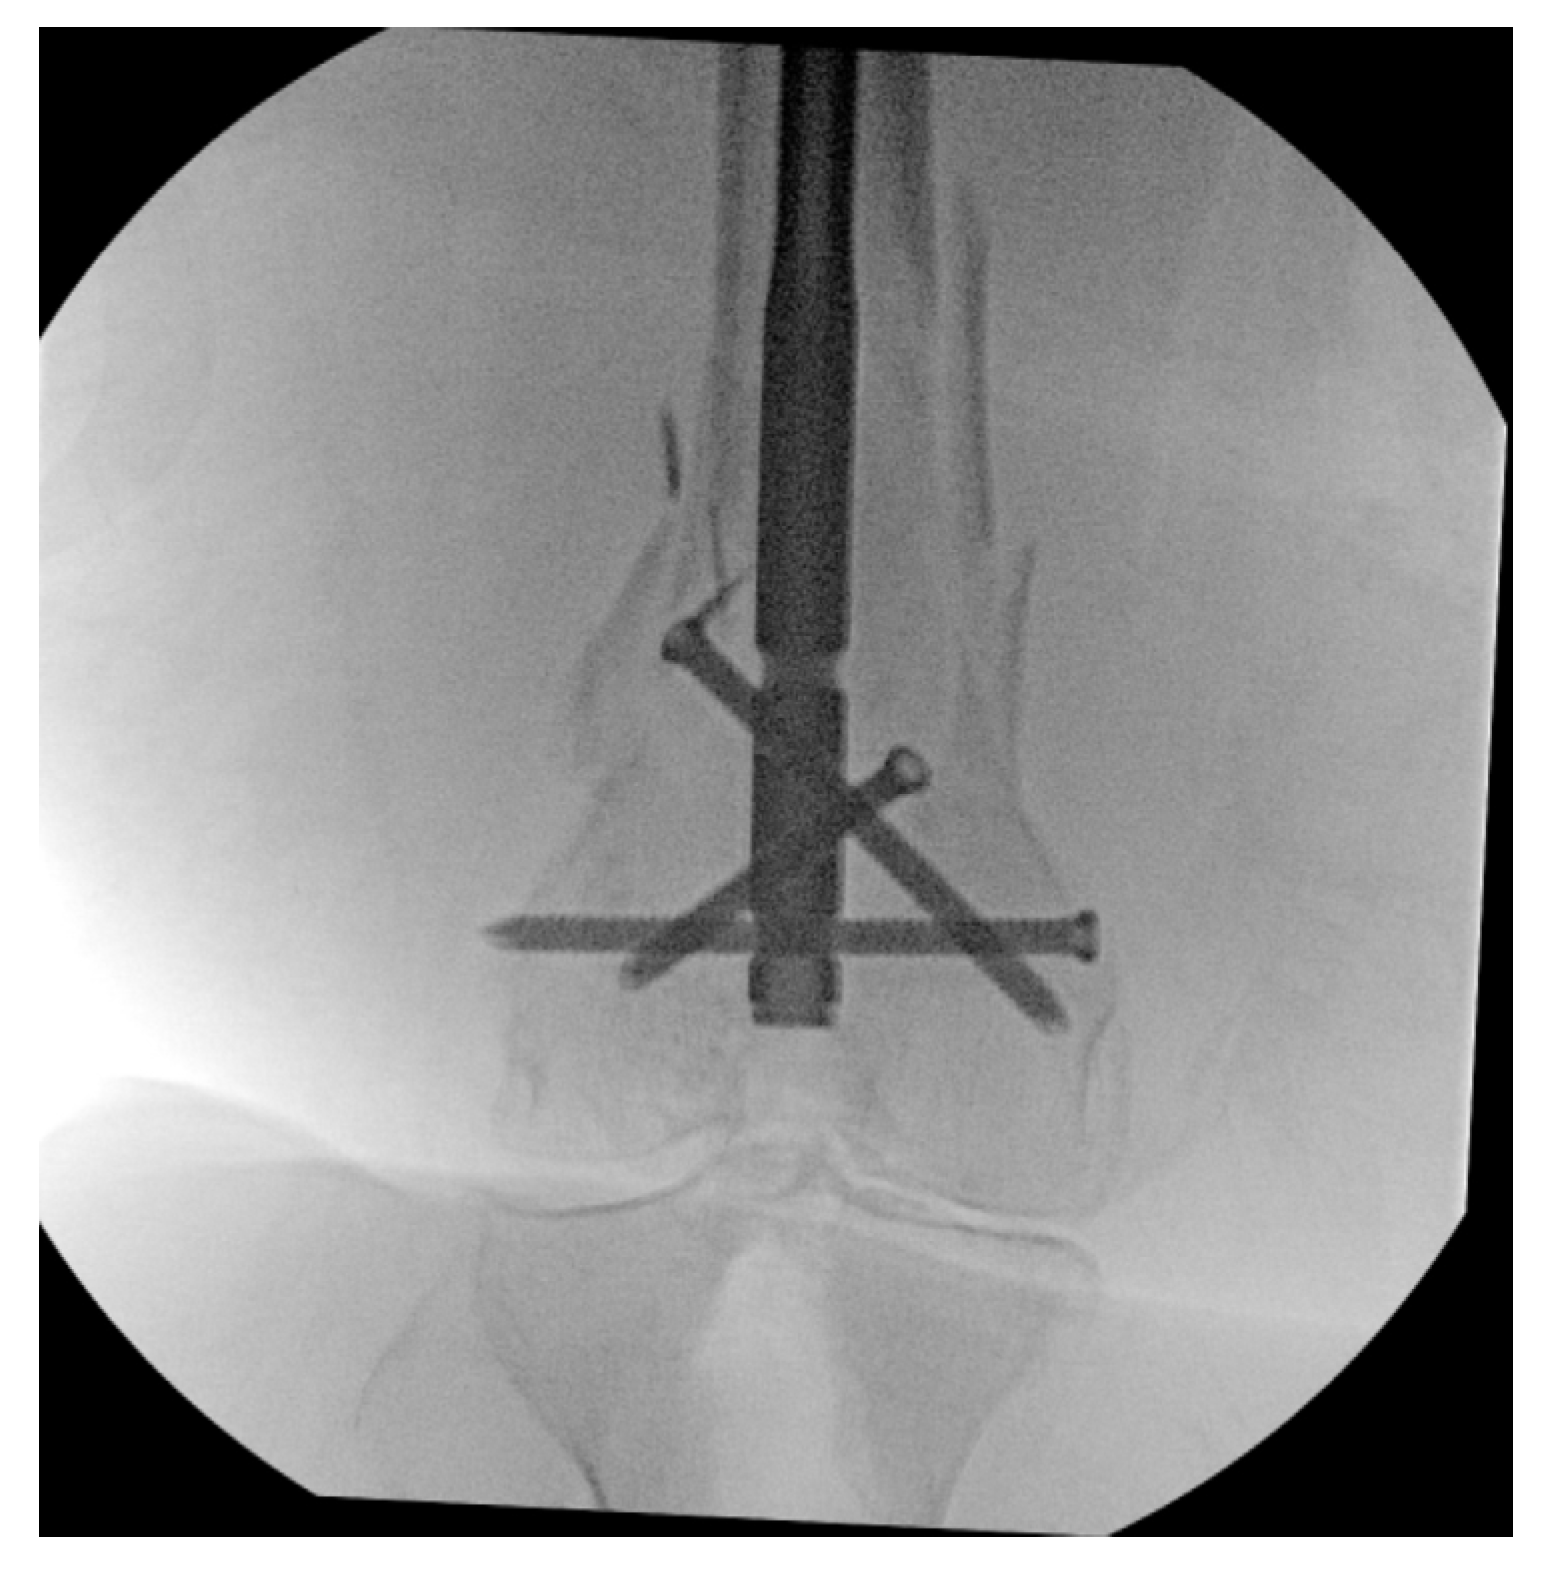

Nail–Plate Constructs for Treating Distal Femur Fractures: A Systematic Review of Biomechanical Studies

3.2. NPCs vs. DP Constructs

3.3. NPCs vs. DLFLP

3.4. NPCs vs. Parallel Plating and Orthogonal Plating

3.5. NPCs vs. Retrograde Intramedullary Nail

3.6. NPCs Using Variable Nail Size

3.7. Linked NPCs vs. Non-Linked NPCs